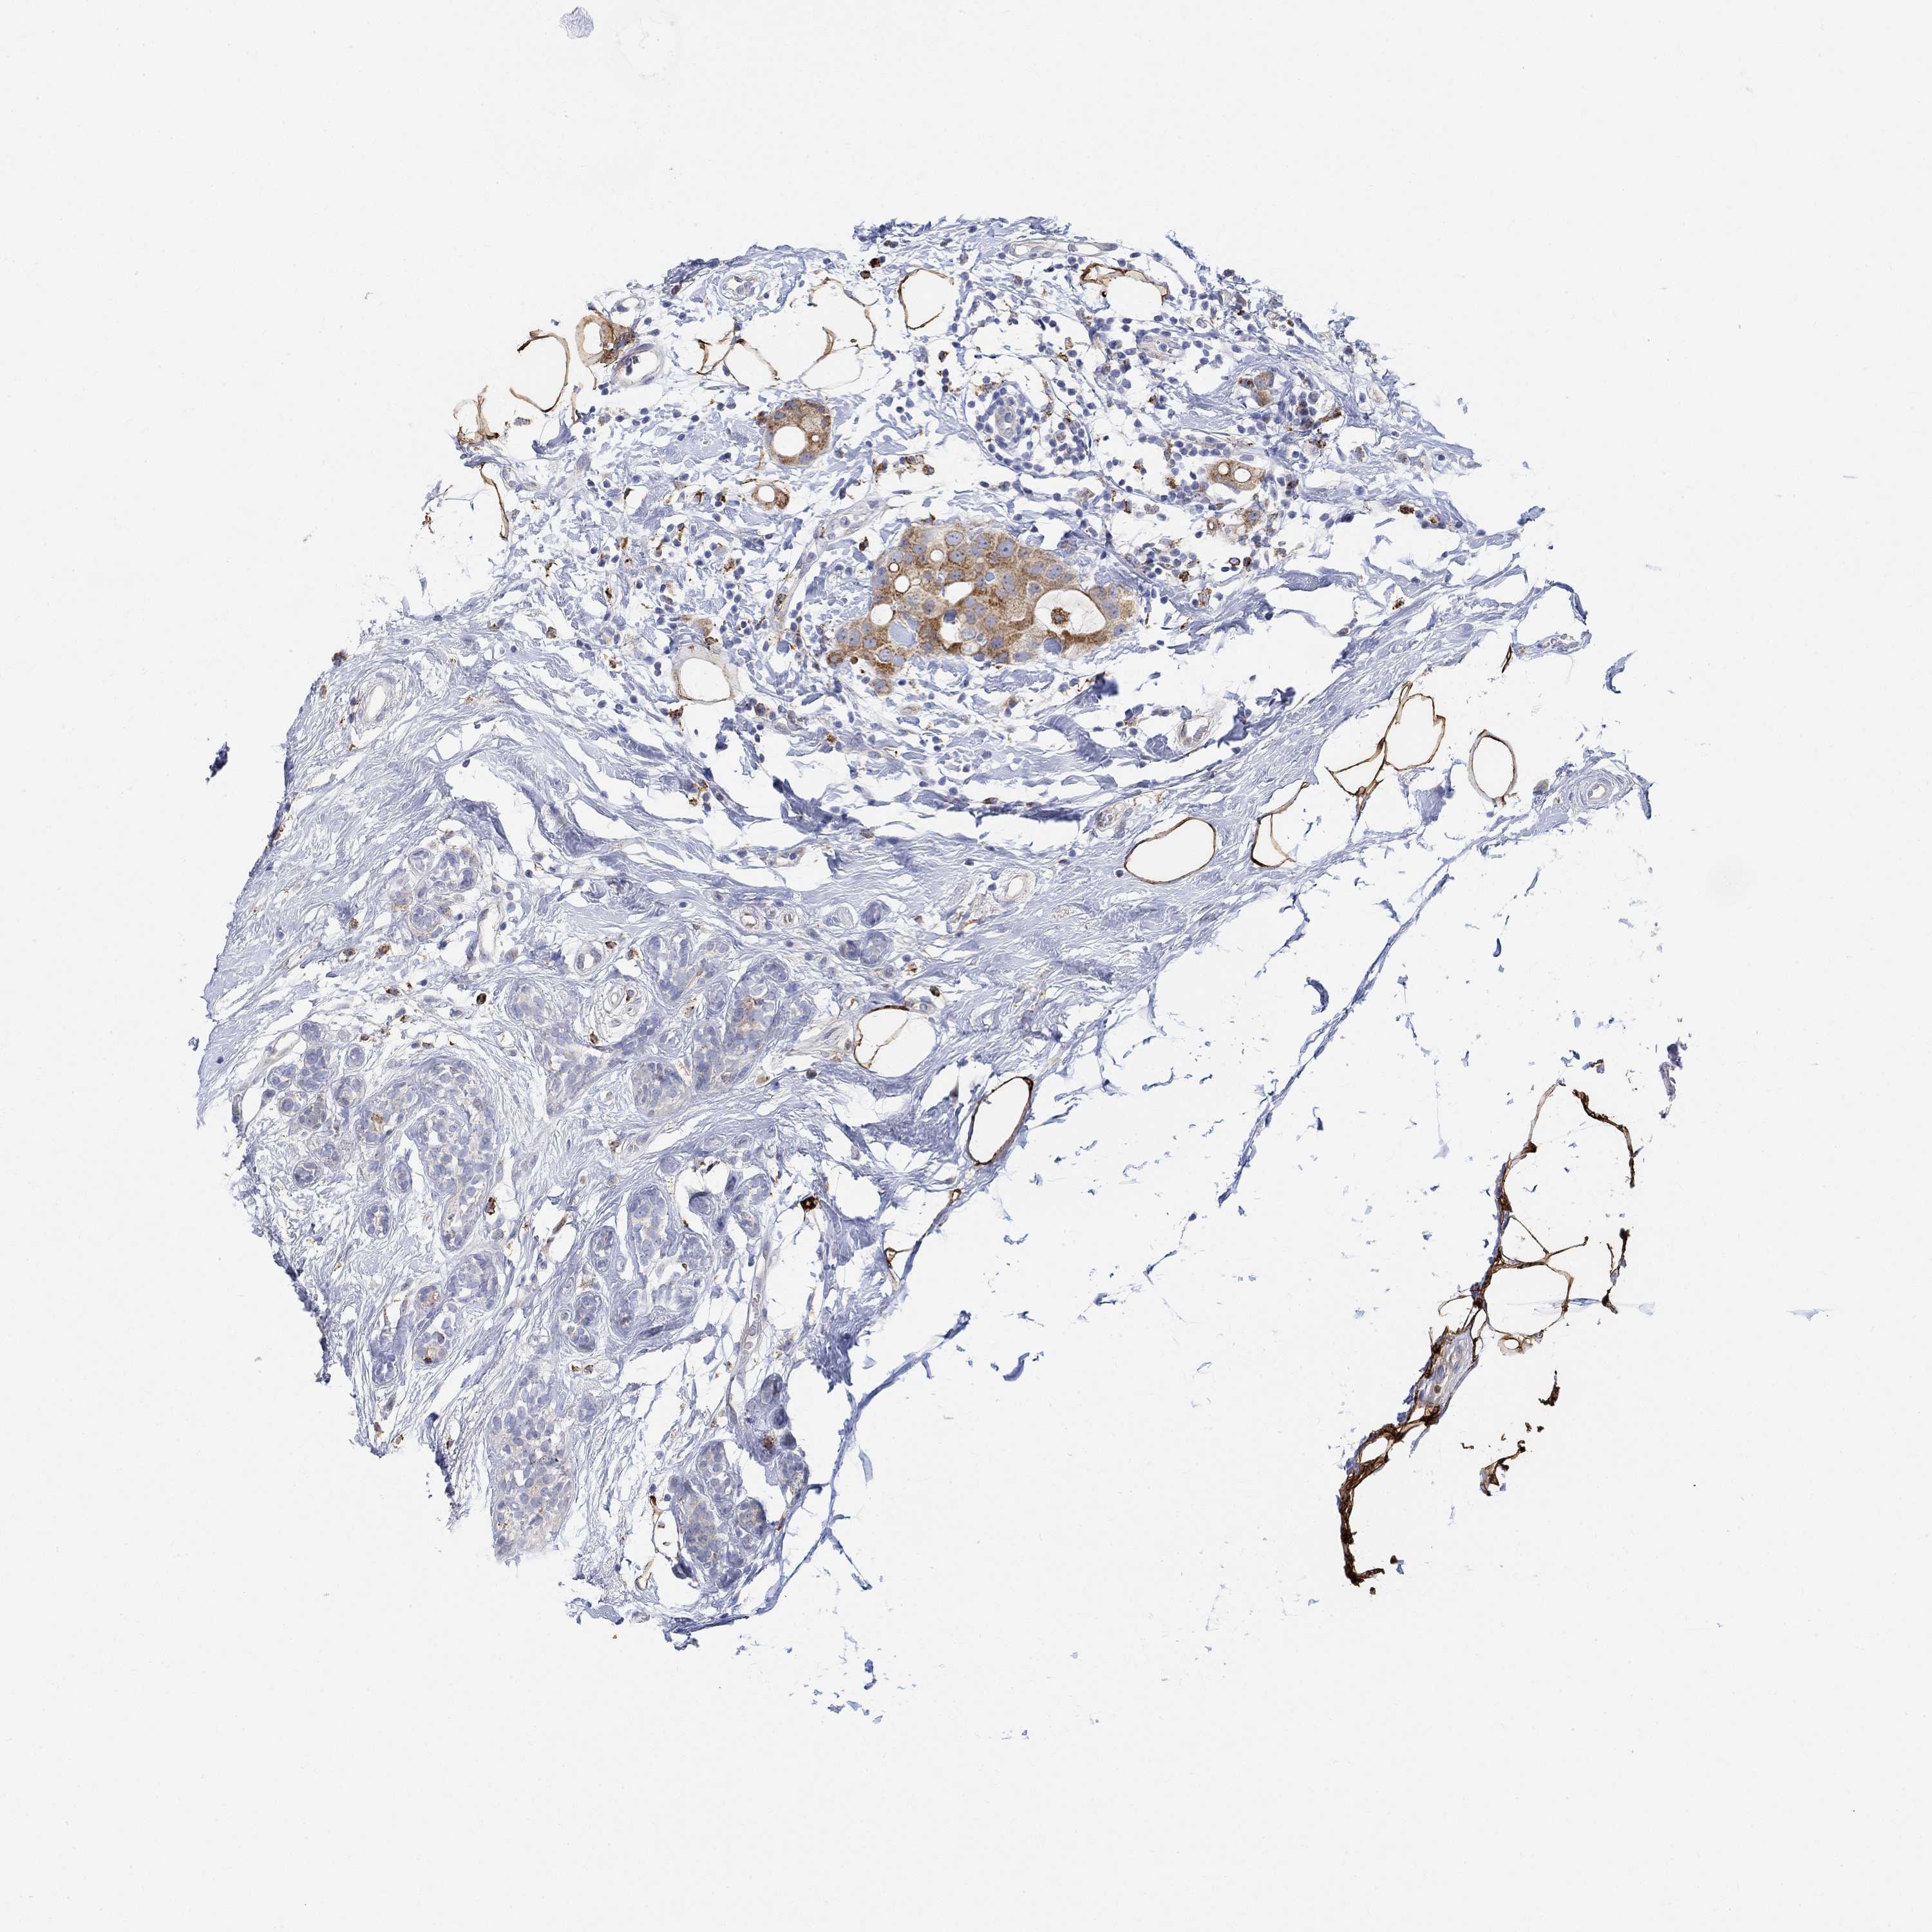

BRCA TCGA BRCA VALIDATION PROTEIN EXPRESSION

ANTIBODIES

AND

VALIDATION